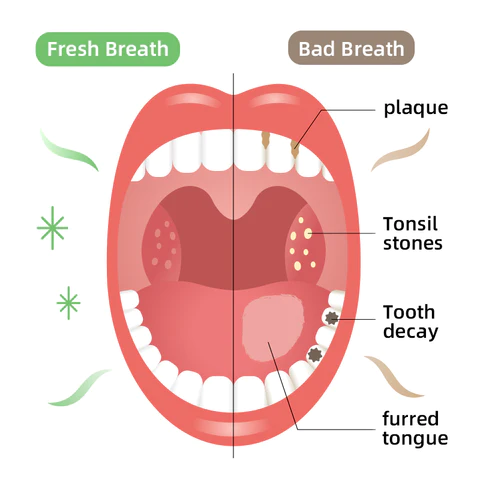

What Causes Poor Oral Health?

Every day, food residues in our mouths create a breeding ground for various bacteria and microorganisms within the oral cavity. This can result in a range of oral health issues, including bad breath, mouth ulcers, yellow teeth, cavities, calculus buildup, gum inflammation, bleeding gums, tooth sensitivity, weakened or missing teeth, swollen gums, toothaches, loose teeth, tooth loss, and even the risk of oral cancer.

As these conditions worsen, you may experience persistent bad breath, gum inflammation, and other problems. Bacteria continue to harm your gums, leading to issues like bleeding, pain, and redness. Without timely intervention, these oral problems can escalate, potentially causing periodontitis, dental plaque, dental calculus, loose teeth, tooth pain, and eventually tooth loss.